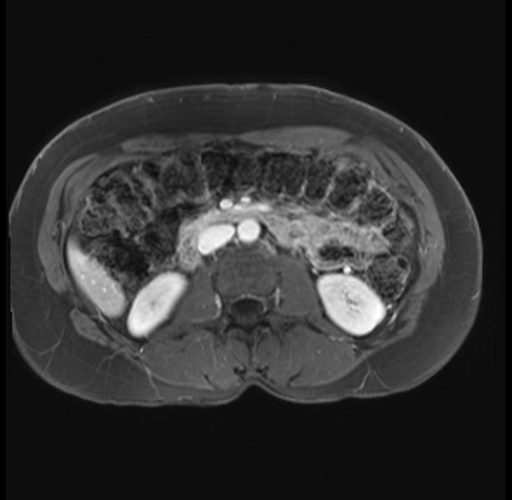

Imaging Analysis

Look through the patient's CT scan to identify any areas of concern for the necessary procedure.

Based on your CT findings, which issue(s) are present and would give reason for "planned slowing down moment(s)" in this case?

Considering a standard distal pancreatectomy procedure, what step(s) of the operation would you do differently in this case?